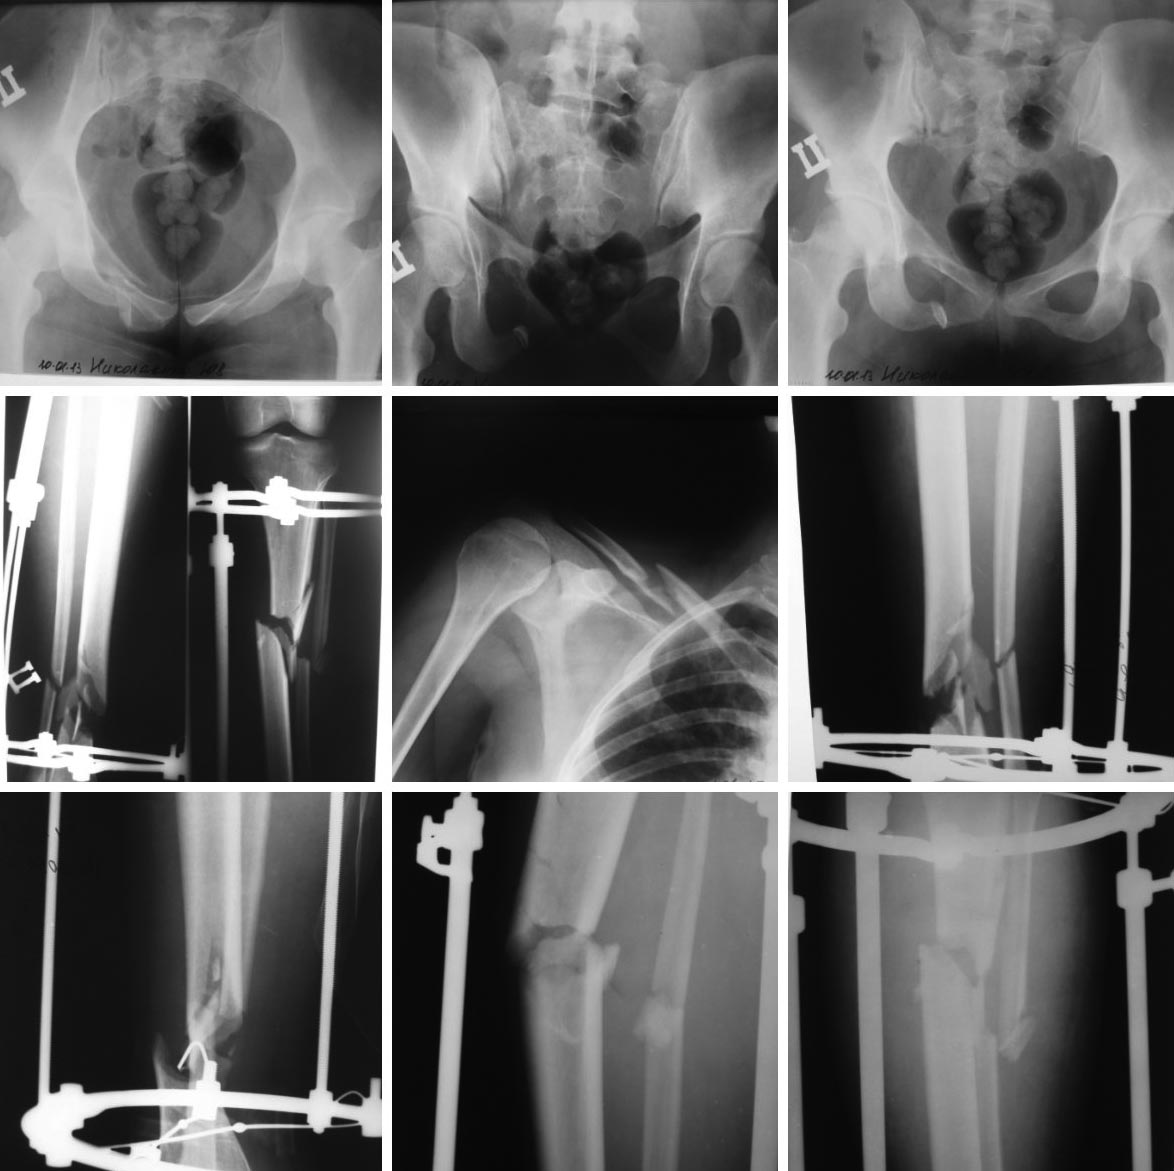

Девушка 27 лет. Автотравма, сбита автомобилем. Диагноз Сочетанная травма: Закрытая травма живота-разрыв правой доли печени. Закрытый перелом верхней челюсти. Закрытый перелом 1-3 ребер справа. Закрытый оскольчатый перелом с\3 правой ключицы со смещением. Ротационно-нестабильное повреждение таза:перелом лонной и седалищной костей справа,перелом латеральной массы крестца справа. Открытый оскольчатый перелом обеих костей правой голени в н\3 с дефектом большеберцовой кости(костные фрагменты скорее всего остались на месте ДТП). Открытый поперечно-оскольчатый перелом в\3 левой голени со смещением.

При поступлении выполнено ушивание разрыва печени. ПХО открытых переломов, фиксация правой и левой голени аппаратами внешней фиксации.

Помогите определиться с дальнейшей тактикой лечения.Наши варианты 1. Чрескостный остесинтез таза-передняя опора. 2.Закрытый интрамедулярный остеосинтез левой голени. 3. а)Чрескостный остеосинтез правой голени аппаратом Илизарова с укорочением голени. После сращения перелома остеотомия, удлинение голени по методу Илизарова. б)Закрытый интрамедулярный остеосинтез правой голени. В последующем в зависимости от состояния сращения перелома-костная пластика. 4.Остесинтез ключицы реконструктивной пластиной.

На представленных снимках невозможно увидеть нестабильность таза, не хватает КТ данных. Здесь травма за счет латеральной компрессии и перелом LC А1. По классификации Young and Burgess относится к стабильным переломам, и такой стабильный перелом не нуждается в операции.

Изолированная травма с LC А1 требует щадящей тактики, и для получения хорошего результата бывает достаточным разгрузка костылем. При политравме нужна опора на костыли, и верхную конечность надо фиксировать как можно скорее. Но на снимке между отломками ключицы видна консолидация, из-за чего также нет нужды в операции.

В данное время надо обратить внимание на переломы голени, и рекомендуется двухсторонняя интрамедуллярная фиксация. Близкий мониторинг с рентгенограммой покажет о необходимости костной пластики. Можно из мини доступов, а о возможности костной пластики в будущем надо обговорить сразу.